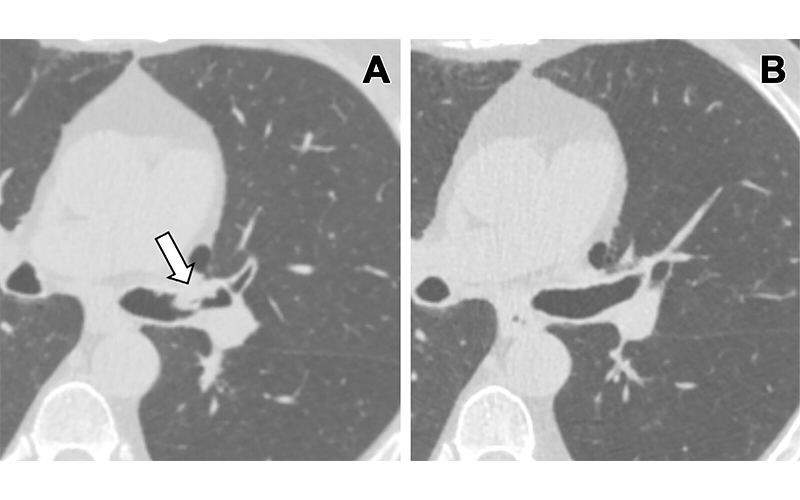

(A) Lung cancer screening CT image (cropped axial plane image, without contrast agent) in a 66-year-old male patient shows a sessile nodule with internal air in the left mainstem to left upper lobe bronchus (arrow) with a mean diameter of 10 mm. The nodule was assigned as Lung Imaging Reporting and Data System category 4A in the clinical report. (B) Follow-up CT image shows the lesion is resolved. https://doi.org/10.1148/ryct.230149 © RSNA 2024